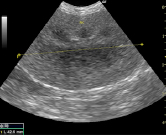

腎臓の超音波検査

超音波検査では腎臓の構造異常や腫瘍の疑いがないかを調べます。腫瘍の可能性があれば超音波で観察しながら注射針を刺して細胞診検査をすることも出来ます。